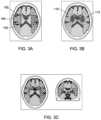

FIGS.3A to3C show slice images of a brain at different stages of processing image data according to the method ofFIG.2;

Atstage46, a bounding cube for a central M region in the atlas data set is determined. The position of middle planar points of anterior and posterior faces of the bounding cube are then determined. These points are referred to as pantand ppost. The boundingcube104 and the points pantandppost100 and102 are shown inFIG.3A, which is a slice image of a brain.

At thenext stage48, for each of the left and right hemispheres, the M1 to M6 regions as labelled in the atlas data set are combined, to obtain a composite M region for the left hemisphere and a composite M region for the right hemisphere. The composite M regions for the left and right hemispheres are indicated inFIG.3B asfeatures110 and112, whereFIG.3B is a further slice image of the brain ofFIG.3A.

FIG.3C shows further slice images, from two orthogonal directions, of the brain ofFIGS.3A and3B, after segmentation using the embodiment ofFIG.2, with different M regions indicated by different shading and boundaries of different M regions indicated by different line styles. The boundary lines are straight at boundaries between those M regions where a clinician would expect to see straight or flat boundaries.